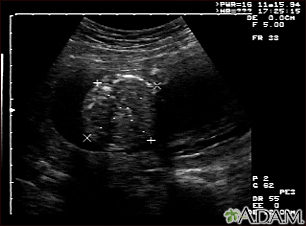

Ultrasound, normal fetus - abdomen measurements